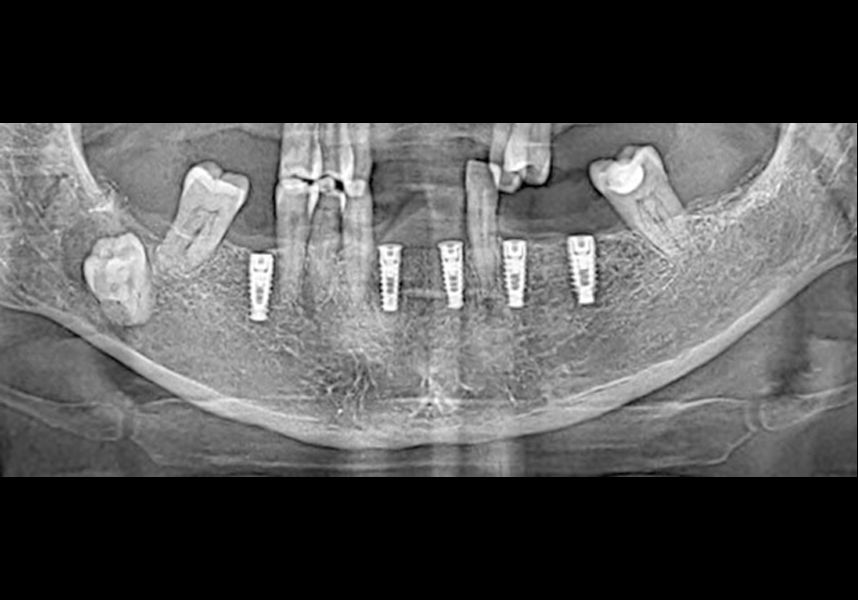

Placement of two dental implants was considered in the anteroinferior area, with simultaneous guided bone regeneration during the same surgery and the subsequent delayed placement of a metal-ceramic bridge for four teeth from 42 to 32. In addition, it was planned to insert three implants in positions 46, 34 and 36, also for restoration with metal-ceramic prosthesis.

The patient was anesthetized and a flap was made from the distal area of tooth 43 up to 36. Then two Avinent Biomimetic Ocean IC implants of 3.5x10 were inserted in positions 32 and 42.

In the posterior sector three Biomimetic Ocean IC implants of 4.0x10 were inserted in positions 36, 34 and 46 with delayed load. A small regeneration was also carried out with autologous bone in the implant in position 34, where there was no exposure, but the vestibular cortical was very fine after implant insertion.

After a post-operative period without complications, the healing abutments were fitted in a second surgical stage 5 months later. Six months after implant placement, the final metal-ceramic prosthetic restoration was loaded.